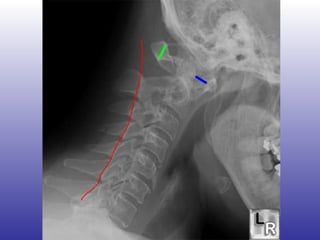

Compromiso cervical Prevalencia: 4-60% FR: Inicio en edades avanzadas Sinovitis muy activa Compromiso erosivo periférico rápidamente progresivo Puede comprometer art. Atlantoaxial y subaxiales (entre C1-C2) Subluxación anterior, posterior o vertical

Compromiso cervical Síntomas subluxación: Cefalea occipital Cuadraparesia espástica Analgesia en manos o pies Episodios autolimitados de disfunción medular Al mover las manos, parestesias en brazos u hombros

Compromiso cervical Signos subluxación: Pérdida lordosis occipitocervical Resistencia a movilidad pasiva Protrusión anormal del arco axial Episodios autolimitados de disfunción medular Signos neurológicos: Reflejos osteotendíneos aumentados Babinsky (+) Debilidad, espasticidad o atrofia muscular

Imagenología Rx cervical lateral  ¿Cuello en flexión? > 3 mm de separación entre el diente del odontoides y el arco anterior del axis Línea espinolaminar hacia posterior en C2

Arco anterior del atlas Arco posterior del atlas Lámina densa Proceso laminar C2 Proceso espinoso C6 Foramen intervertebral C7-T1 Espacio retrofaríngeo  (Normal < 7mm) Espacio retrotraqueal (normal  <2cm).

Imagenología Rx cervicallateral ¿Cuello en flexión? > 3 mm de separación entre el diente del odontoides y el arco anterior del axis Línea espinolaminar hacia posterior en C2

Arco anterior delatlas Arco posterior del atlas Lámina densa Proceso laminar C2 Proceso espinoso C6 Foramen intervertebral C7-T1 Espacio retrofaríngeo (Normal < 7mm) Espacio retrotraqueal (normal <2cm).

• #101 Lat eral radiograph of the neck with the head in flexion shows an increased distance between the anterior border of the dens and the posterior border of the anterior tubercle of C1 (blue line) from ligamentous laxity caused by rheumatoid arthritis. The &amp;quot;pre-dentate space,&amp;quot; as this is called, should be less than 3 mm in the adult. The red line above should smoothly connect all of the spinolaminar white lines of each vertebral body but clearly is directed posterior to the spinolaminar white line of C1 (green arrow) since C1 is subluxed forward on C2.